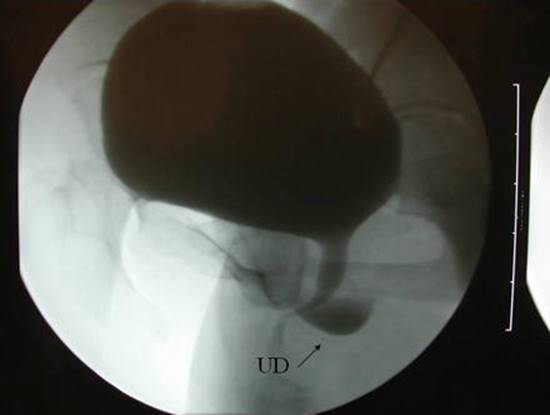

A number of imaging techniques have been applied to the study of female UD. Currently available techniques for the evaluation of UD include double-balloon positive-pressure urethrography (PPU), voiding cystourethrography (VCUG) (Fig. 11.4), intravenous urography (IVU), ultrasound (US), and magnetic resonance imaging (MRI) (Fig. 11.5), with or without an endoluminal coil (eMRI). MRI has become the imaging modality of choice in many centers due to its relatively noninvasive nature, and ability to visualize the anatomy in multiple planes [30–32].

Fig. 11.4

A voiding cystourethrogram demonstrates a urethral diverticulum (Used with permission from Rovner ES. Urethral diverticula. In: Female Urology, 3rd ed. Edited by Raz S, Rodriguez LV. Philadelphia: Saunders Elsevier; 2008)